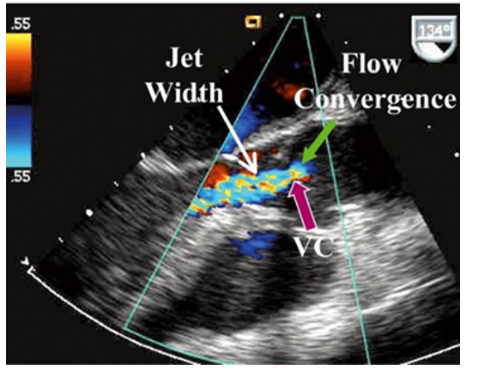

How do you assess Vena Contracta for Aortic Insufficiency?

Vena contracta: narrowest part of the jet in the area between the proximal flow convergence zone and the regurgitant jet

Steps:

measure in PLAX

Zoom in on the aortic valve and LVOT

store cine that shows flow convergence dome, VC, and regurgitant jet

freeze and measure the narrowest portion of the AI jet